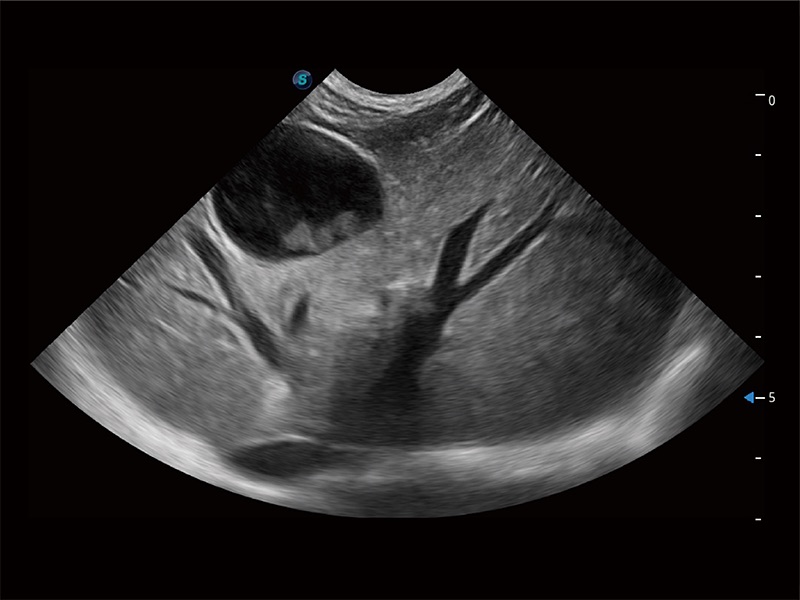

高性能和先进的临床应用工具可以为动物医生提供临床信心。ProPet 80 搭载了先进的腹部和浅表应用工具,帮助医生在日常临床实践中发挥前所未有的作用。

ProPet 80 全新的动物超声智能软件和丰富的探头群,为动物医生提供了高清晰度和精细分辨率的图像,无论在宠物、马科、畜牧还是实验室动物等应用中都可以轻松应对,为您的日常工作带来满意的体验。